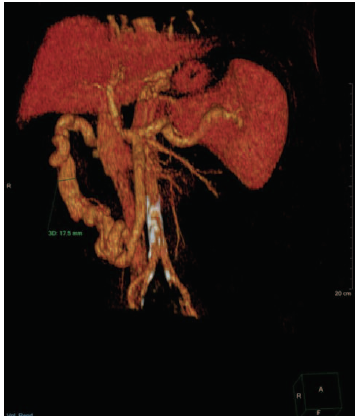

At the end of the procedure, a regular hepatopetal flow was obtained, with total occlusion of the mesocaval and coronary shunts (Figure 3). The interventional procedure lasted 3 hours, and no intraoperative complications were observed.

Figure 3. Regular Hepatopetal Flow Shown After Embolization